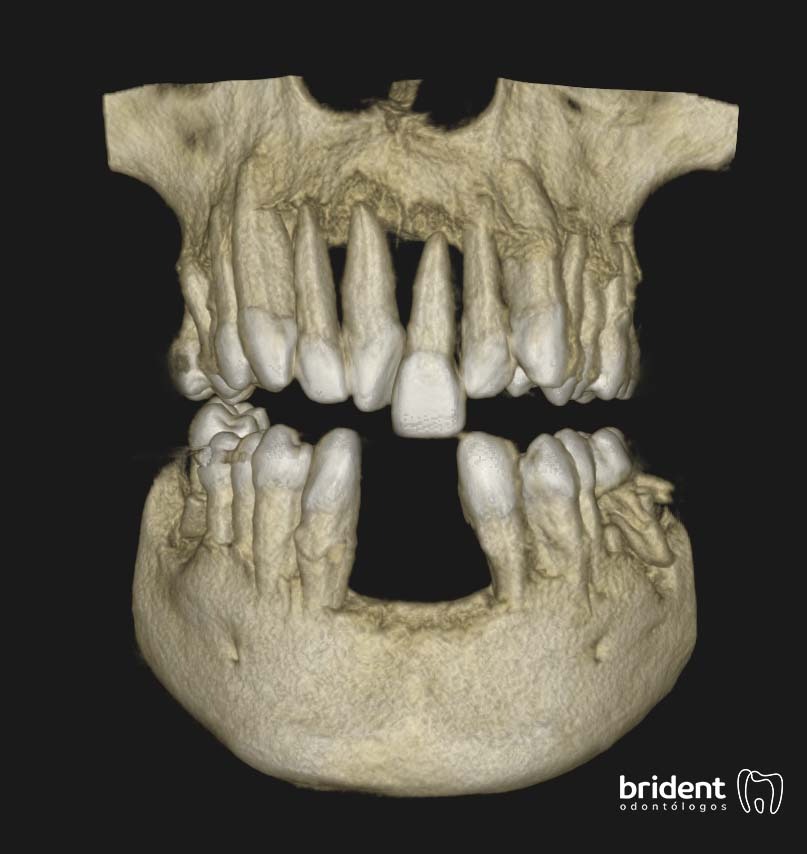

Tras un examen clínico y en algunos casos la realización de un Tac dental 3D o una Ortopantomografía, nuestro experto en periodoncia llevará a cabo una valoración y un plan de tratamiento personalizado para cada paciente.

1. DIAGNÓSTICO

Realizamos radiografías o un tac 3D y una serie de pruebas clínicas con una sonda periodontal para diagnosticar si existe enfermedad periodontal o no.